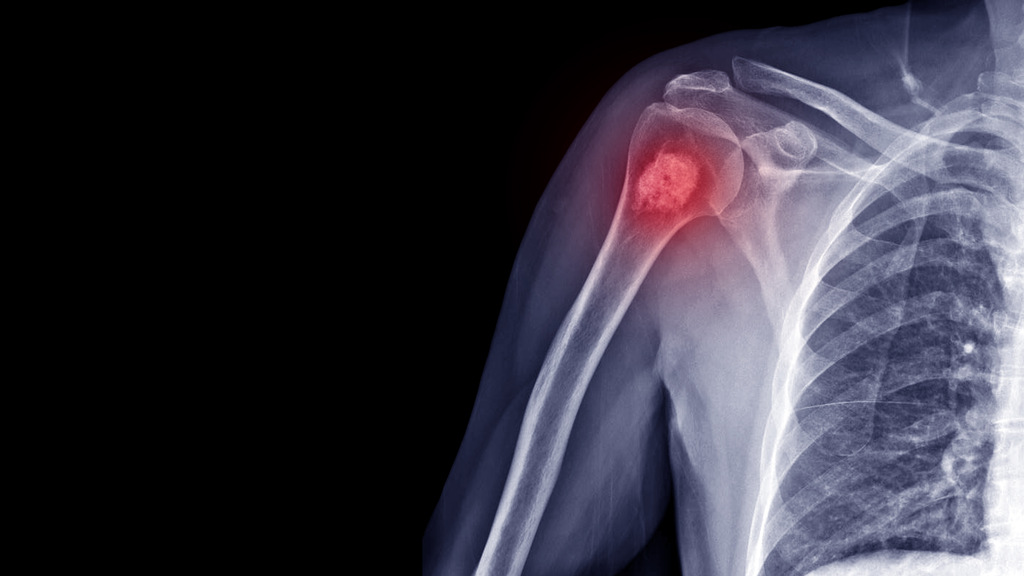

Pessoas com osteoporose têm maior risco de câncer ósseo?

Isso é parcialmente verdade, já que embora a osteoporose em si não cause câncer ósseo, a fragilidade dos ossos associada à doença pode aumentar o risco de fraturas patológicas.

Essas são fraturas que ocorrem em um osso enfraquecido por uma doença ou um medicamento, sem um trauma significativo.

Em alguns casos raros, podem revelar a presença de um câncer que se originou em outra parte do corpo e se espalhou para os ossos, causando metástases ósseas.

As metástases ósseas são mais comuns em cânceres de mama, próstata, pulmão, rim e tireóide.